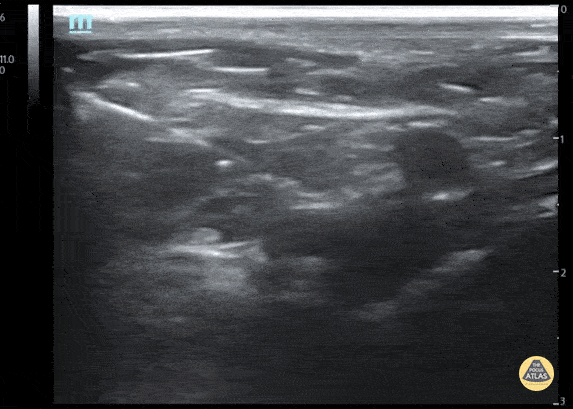

Fascia Iliaca Nerve Block

Fascia iliaca nerve block for 3yo M with left femur fracture

Contributor: Julia Brant, MD, Children's Hospital Colorado, @pedipocus